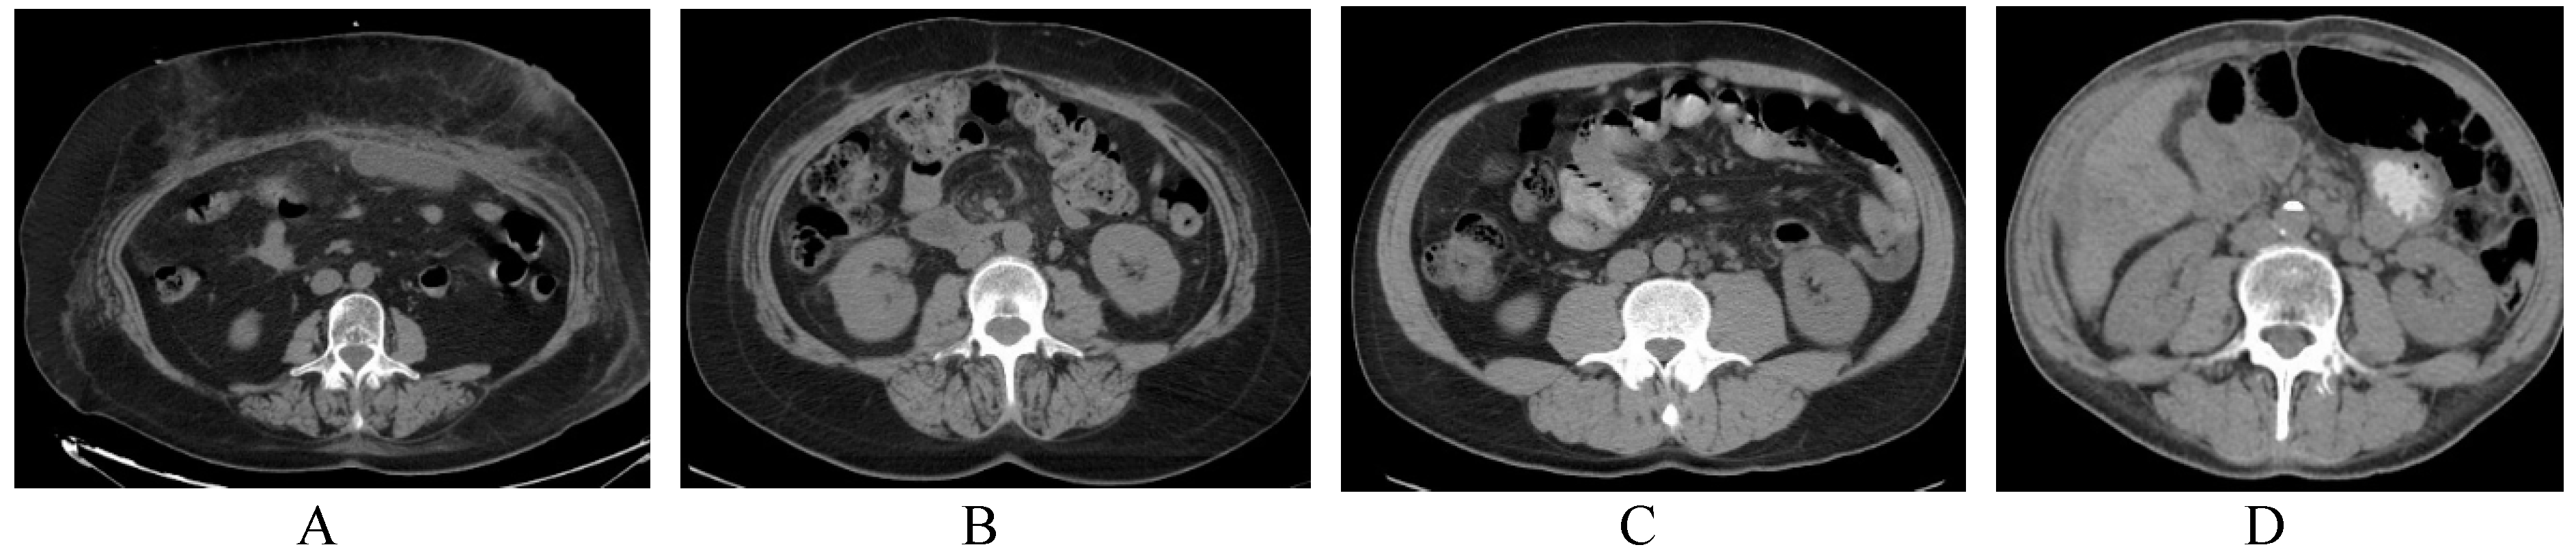

2.2. Assessment of Skeletal Muscle Mass